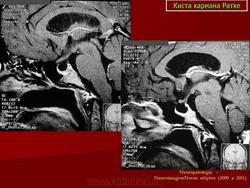

ГМ. Киста кармана Ратке. +

Киста кармана Ратке

Киста кармана Ратке ИМХО должна иметь стенку. На первой серии снимков верхней стенки нет и киста сливается с супраселлярной цистерной, имеет неотличимые от ликвора сигнальные характеристики. Насчёт подстверждения. Вот интересно мне, как можно подтвердить кисту кармана Ратке в данном случае?? Гистологически?

Мне тоже показалось, что в первой серии изображений кистой и не пахнет.Видится "пустое" турецкое  седло с расширенной  супраселлярной цистерной.Оказалось, что не только мне одной.